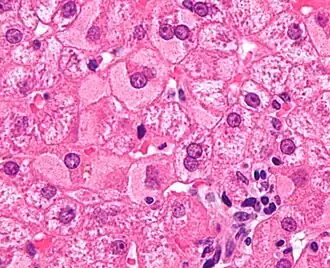

Una hepatopatía previa no diagnosticada se puede detectar tras la autopsia. Abajo se muestran imágenes de la patología:

-

Cirrosis difusa -

Cirrosis macronodular -

Textura de nuez moscada de la hepatopatía congestiva -

Metástasis hepáticas